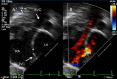

This review article will guide the reader through the basics of echocardiographic assessment of congenital left to right shunts in both paediatric and adult age groups. After reading this article, the reader will understand the pathology and clinical presentation of atrial septal defects (ASDs), ventricular septal defects (VSDs), atrioventricular septal defects (AVSDs) and patent arterial duct. Echocardiography is the mainstay in diagnosis and follow-up assessment of patients with congenital heart disease. This article will therefore describe the echocardiographic appearances of each lesion, and point the reader towards specific features to look for echocardiographically.